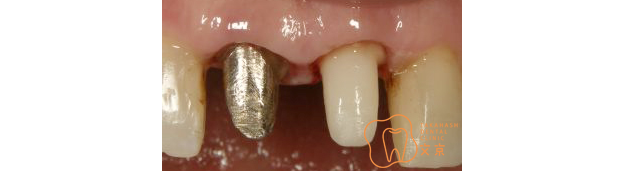

■歯の基礎となるコア 接着性能を向上させたファイバーコア

■前歯が折れてしまった、、、